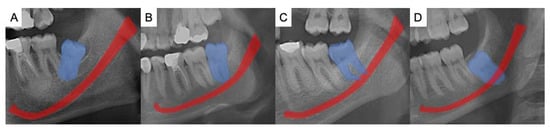

The data set was divided in half for each observer, and two independent dentomaxillofacial radiologists annotated the MCs and M3s in the OPGs via the annotation tool MATLAB (The MathWorks, Inc., Natick, Massachusetts, USA). Under dim light conditions, both observers used different but analogous monitors for the labeling task (2560 × 1600 pixels, 13-inch high-resolution Retina display MacBook Air laptop, California, USA). Both left and right M3s and MCs were labeled. The same observers also classified each labeled region for the extent of M3 root-tip overlap with the MC according to the published method [12]. The classification was as follows; I: No connection, II: Direct contact with superior cortical boundary, III: Superimposed, IV: Root tip is under the inferior cortical line (Figure 1).

Figure 1. The examples for the classification of the relationship between the mandibular third molar (blue area) and mandibular canal (red area). (A) represents class I where there is no connection between the root tip and MC. (B) represents class II where the direct contact of M3 with the superior cortical boundary of the MC. (C) represents class III where the M3 and MC are superimposed and the (D) represents class IV where the root tip is under the inferior cortical line of MC.